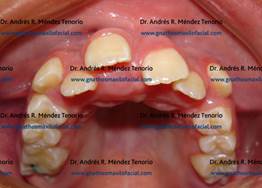

| Paciente con malposiciones dentales múltiples que requiere ortodoncia | |

| El origen de la malposicion en este caso, es porque se desarrollaron dientes incisivos supernumerarios | |